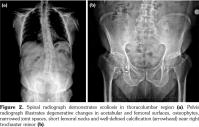

A 42-year-old male patient was examined due to gait difficulty and pain in hip and knee joints bilaterally and low back. He declared that he could walk independently, yet he had some difficulties in walking on undulating surfaces or climbing up stairs. Medical and family history was noncontributory. He was 168 cm tall and weighed 78 kg. Physical examination revealed severe restriction of range of motion in hip joints, crepitation in knee joints, hyperextension position of the first metacarpophalangeal joint, and deviation of the thumbs. Adam’s test for scoliosis was positive and lumbar motions were limited as well. Minimal joint effusion was detected in knee joints as well. Knee radiographies showed double- layered patella (DLP), generalized degenerative changes, scoliosis, and circumferential radiopaque lesion around the right hip joint (calcification of the iliopsoas bursa) (Figures 1 and 2). Magnetic resonance imaging designated the association between the quadriceps tendon and patella (Figure 3). Laboratory investigations including erythrocyte sedimentation rate and C-reactive protein, calcium, phosphate, and alkaline phosphatase levels were all within normal limits. Overall, the patient was diagnosed with secondary OA due to MED and referred to another center for further genetic analysis. A written informed consent was obtained from the patient.